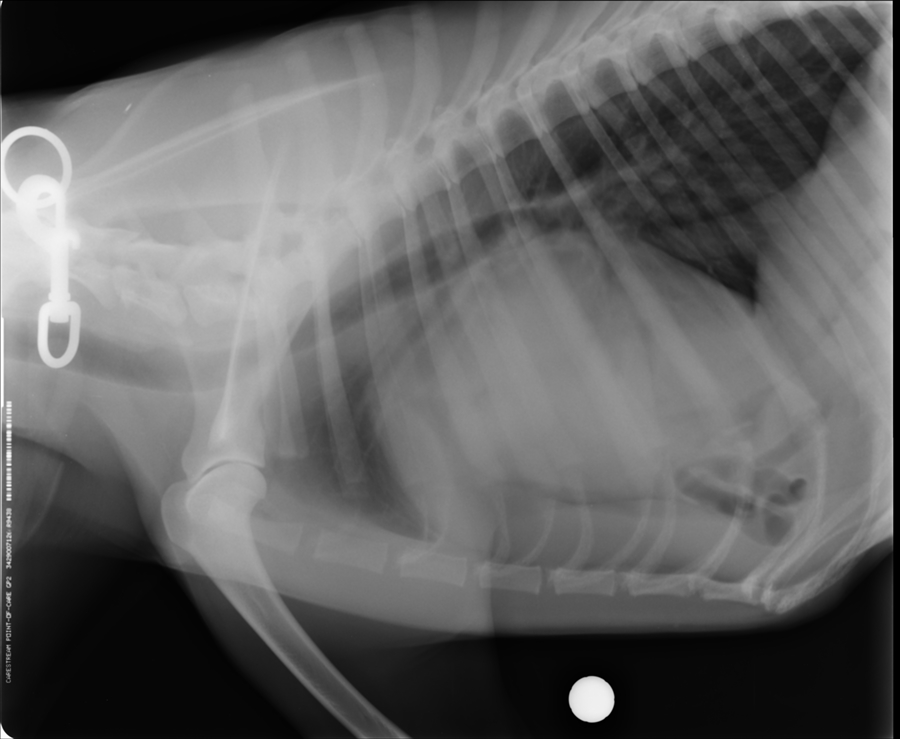

Su veterinario realiza estudio radiográfico de tórax y observa asas intestinales en tórax. No se observa claramente la silueta cardíaca. Por ello, se solicita a Dxia que lleve a cabo un estudio ecocardiográfico y una ecografía torácica no cardiaca.

Radiografía hernia peritoneopericárdica

Al realizar estudio ecográfico se observa la presencia de asas intestinales de ID junto con el bazo, confirmándose la existencia de hernia peritoneopericardio-diafragmática. Esto es una malformación congénita que puede coexistir con otros defectos congénitos (no se realiza estudio abdominal pero la propietaria comenta que ambos testículos son ectópicos, aunque esto no se considera defecto congénito). Se recomienda realizar estudio ecocardiográfico.